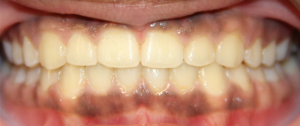

Before and After photos: Crossbite Treatment